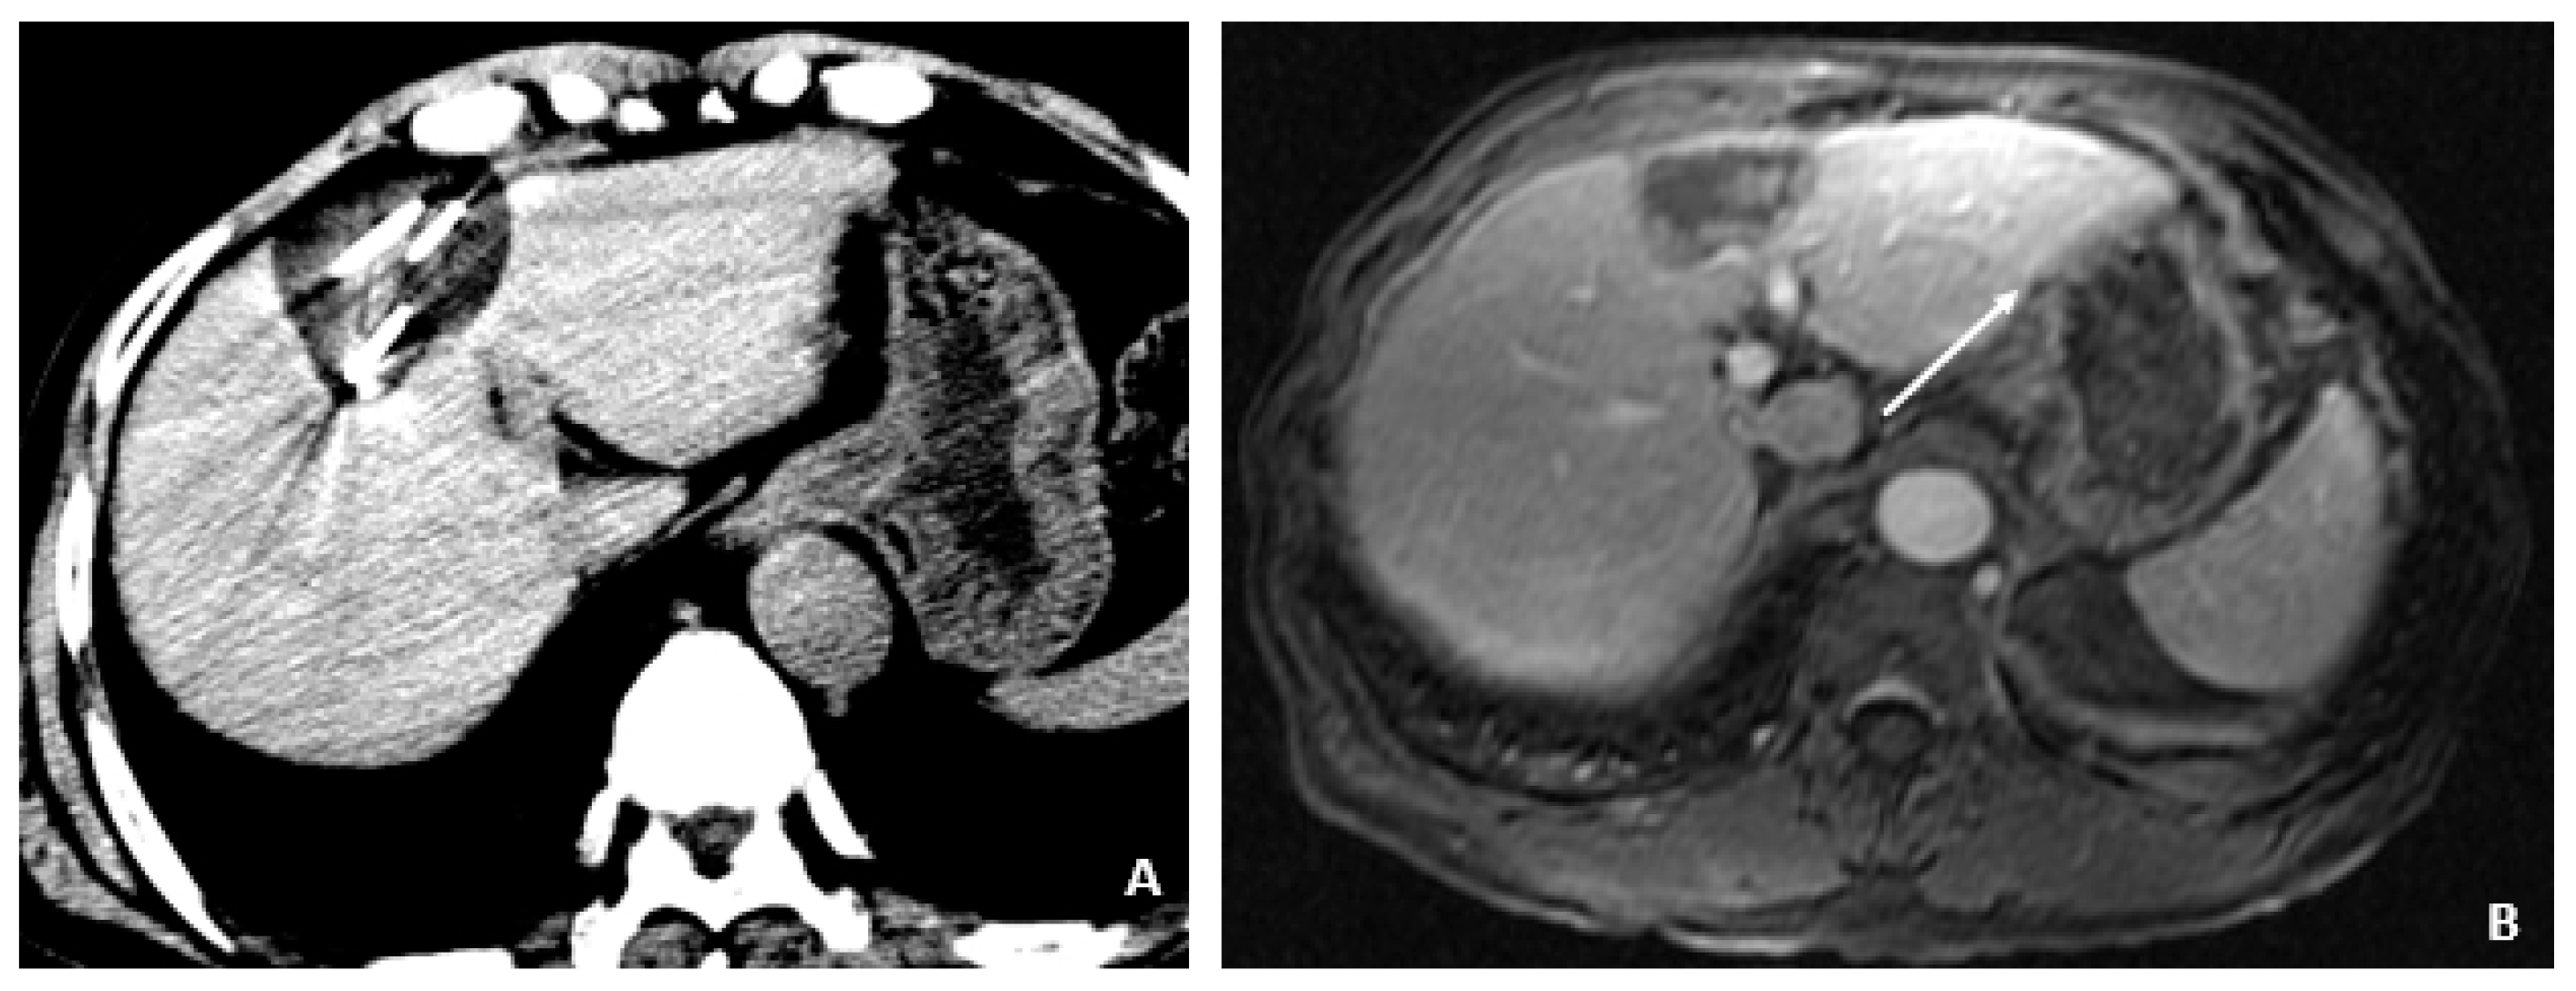

A 50-year-old male was diagnosed with CHB at age 40. With lamivudine treatment for 3 years, he achieved HbsAg seroconversion to anti-HBs and lamivudine was discontinued. Table 4 outlines his course. Five years later, on a follow up examination he was found to have HBV DNA 847 copies/mL, ALT 33 IU/L, and AFP 20.5 ng/mL. An MRI (December 2009) showed a 5 cm lesion consistent with HCC (Figure 1A,B). Repeat AFP was 17.8 ng/mL at time of HCC diagnosis, and AFP-L3% was 75.6. He underwent transarterial chemoembolization (TACE) with successful resolution (Figure 2A,B) and restarted lamivudine. The AFP remained at 3.0 ng/mL, and the MRI showed no evidence of HCC the following year. Two years after initial treatment, the AFP increased to 5.9 ng/mL with 57.5% L3. The MRI next month showed recurrent HCC at the treated site (Figure 3). The patient underwent laparoscopic radiofrequency ablation and therasphere treatment.

Figure 1.

MRI at the time of diagnosis of HCC (December 2009). (A) The coronal T2-weighted image shows a mildly heterogeneous mass in the left hepatic lobe (arrow), corresponding to hepatocellular carcinoma. (B) The axial T1-weighted fat-suppressed arterial-phase postcontrast image shows faint foci of hyperenhancement within the lesion, characteristic of HCC.